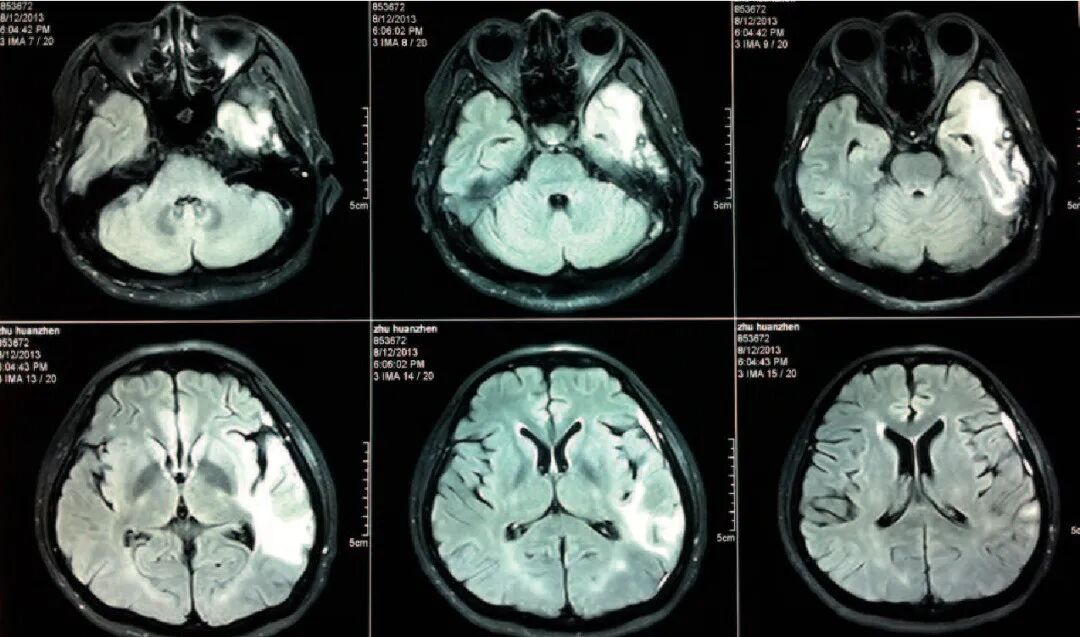

在很多外国口音综合征案例中,共同之处是大脑左半球的特定区域有损伤,而普通人的语言功能区就位于左半球。当然,脑损伤都是很随机的,在被报告的外国口音综合征中,有三分之二的患者还有其他的语言缺陷症状,比如失语症,阿斯特丽德的案例正是如此。不过,在少数情况下,外国口音综合征也可能会由心理疾病引起,而不是对大脑的物理损伤。如果是心理疾病引起的,那么在治愈其相应的病症后,比如转换障碍或精神分裂,外国口音自然也会消失。